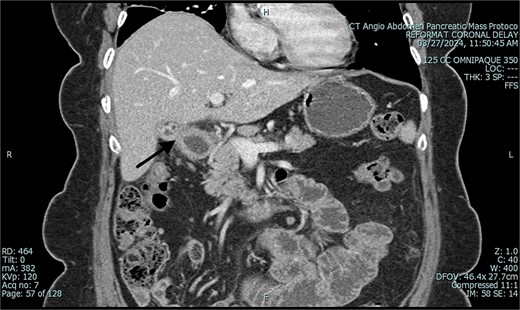

A 67-year-old female patient with a past medical history significant only for C-section, presented with 1 week of intermittent abdominal pain, distension, and nausea with vomiting. Vital signs were in the normal range. Physical exam was notable for a soft and nondistended abdomen with right lower quadrant tenderness. Laboratory studies were unremarkable. Radiological imaging (Figs 1 and 2) demonstrated a developing SBO.

Preoperative CT of abdomen in coronal view, demonstrating small bowel obstruction.